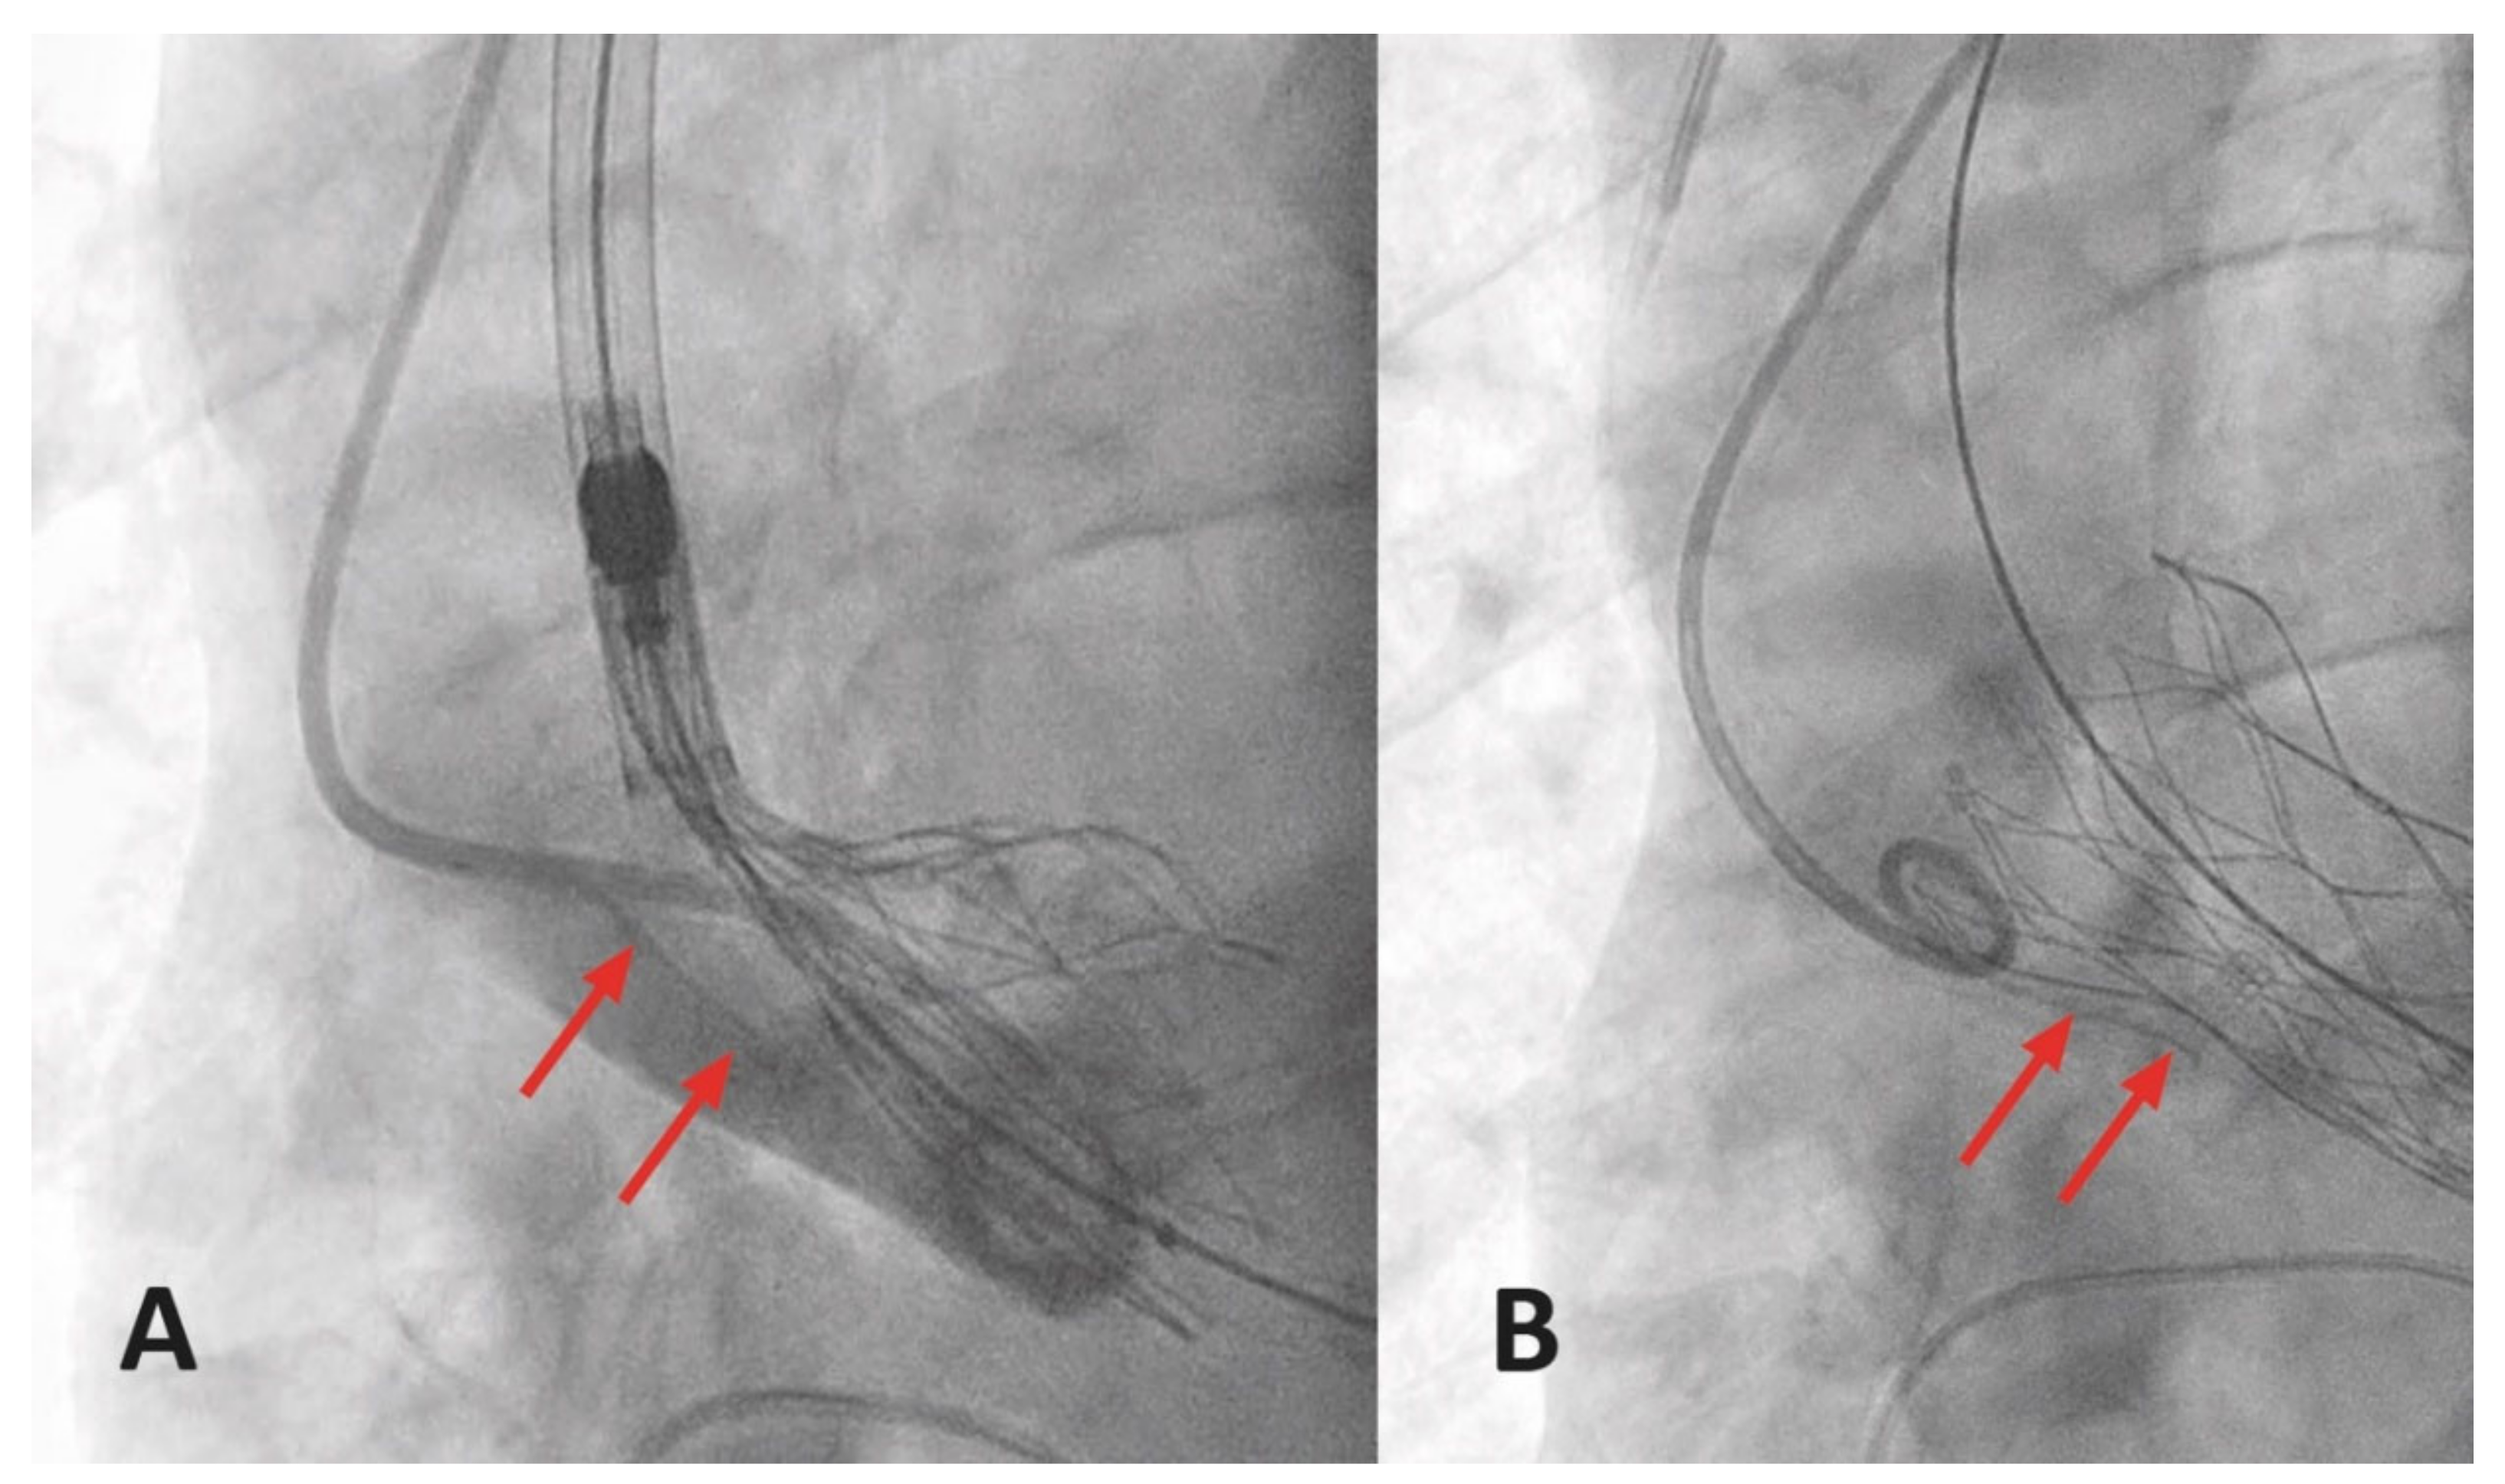

3.6.6. Closure Device Failure